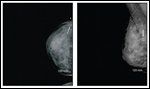

A 30-year-old female at 6 weeks’ gestation of a highly desired pregnancy presented to our multidisciplinary breast cancer clinic with a new diagnosis of invasive ductal carcinoma of the right breast. The patient had just become aware of her pregnant state when she noted a mass in her right breast on self-examination. She was evaluated with a diagnostic mammogram with proper shielding and an ultrasound, confirming a 1.4-cm solid mass corresponding to the palpable lesion (Figures 1 and 2). Ultrasound-guided core needle biopsy was obtained and revealed a grade 3/3 invasive ductal carcinoma, estrogen receptor (ER)-negative, progesterone receptor (PR)-negative, and human epidermal growth factor receptor 2 (HER2)-negative. On physical exam, she showed changes to the breast tissue consistent with early pregnancy, a palpable mass at the biopsy site, and no axillary adenopathy or contralateral findings. The remainder of her examination was likewise benign.

FIGURE 1

Diagnostic MammogramFIGURE 2

Dr. Jennifer Diamond: Ultrasound is ideal in evaluating a breast mass during pregnancy as it poses no risk to the fetus and has a sensitivity for malignancy approaching 100%.[1-3] Mammography also poses little risk to the fetus and is considered to be a safe imaging technique in pregnancy if necessary. The dose of radiation to the fetus with a standard bilateral mammography using abdominal shielding has been estimated at 0.004 Gy of radiation, falling well below the threshold for malformation in the fetus of 0.05 Gy of radiation.[4] The earlier in pregnancy, the lower the exposure to the fetus.

Dr. Laura Hardesty: Mammography is recommended for several reasons in this scenario. Although it is known that cancer is present at the site of the palpable mass, evaluation of the remainder of the ipsilateral breast and of the contralateral breast for the presence of additional sites of malignancy is necessary. Mammography allows for a “whole breast” view that cannot be obtained by sonography. Even if screening sonography of the entirety of both breasts is performed, only small portions of the breasts are imaged at one time. The radiologist must mentally “synthesize” a summary view of the breasts. As a result, mammography may provide a more complete understanding of the three-dimensional location of the cancer within the breast, particularly if there is more than one mass suspicious for cancer.

In addition, mammography is markedly more sensitive than sonography for detecting small calcifications that may indicate malignancy extending beyond the size of the sonographically imaged tumor, often ductal carcinoma in situ (DCIS). The difference in tumor size detectable by mammography vs sonography may also be significant, thus affecting treatment decisions regarding lumpectomy vs mastectomy.

In general, the mammographic density of the breasts increases with pregnancy-induced breast changes. This decreases the sensitivity for detecting breast masses, but does not decrease the ability to detect cancer-associated calcifications. The increase in mammographic glandular density becomes more marked as the pregnancy progresses, and is unlikely to be a limiting factor at 6 weeks’gestation